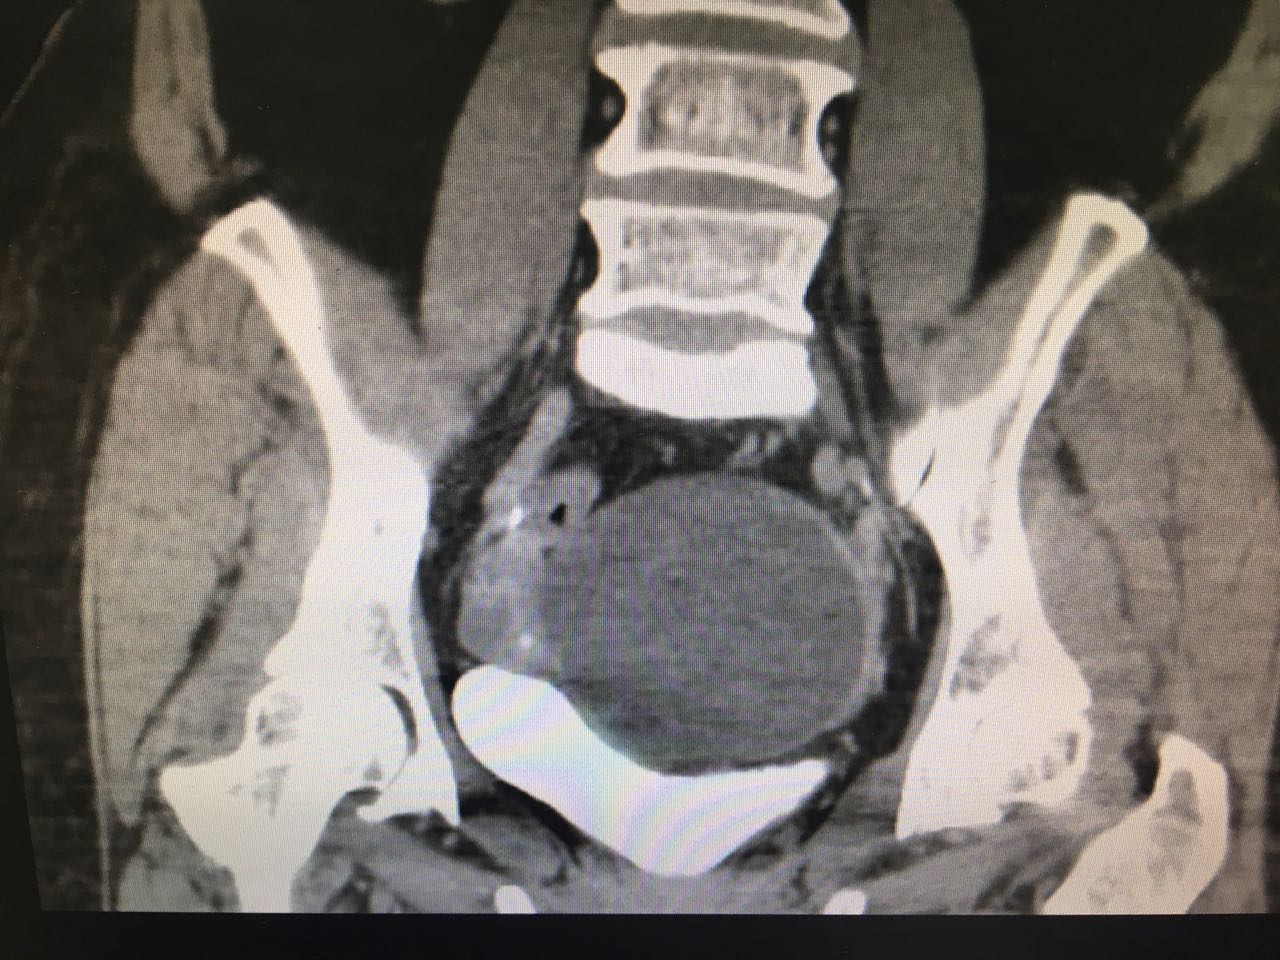

1、 患者女性,58岁  2、 主诉:发现盆腔肿物3月余;  3、 现病史:3-0-0-3,绝经2年。患者2015年体检未见明显异常,3月前体检时发现下腹部有一包块,无腹胀腹痛,无阴道出血,无阴道流液,无尿频尿急。查【妇科超声】示:左附件囊肿,卵巢囊腺瘤可能(子宫后上方无回声区116*94*110,形态规则,边界清晰,内壁光滑,后方回声增强,内见回声隔分隔成两房,隔上未见明显血流信号),【TCT】未见上皮内病变细胞或恶性细胞,肿瘤标志物检查未见异常。后行阴道镜检查示:宫颈转化区II型,宫颈活检病理报告:宫颈3、6、9、12点为黏膜慢性炎。现患者为求进一步诊治,门诊拟“左附件囊肿”收治入院。 自发病以来,患者精神可,一般情况可,睡眠可,胃纳可,二便基本正常。

4、妇科体检: 外阴(-);阴道畅;宫颈光,局部宫颈活检后改变;宫体:前位,偏向左侧,萎缩,表面光滑,活动可;子宫左上方可及囊性肿块直径8cm左右,质软,活动尚可,无压痛,右附件区未及明显异常。  5、辅助检查: 生化、血常规、阴道分泌物、内分泌检查未见异常 【TCT】:未见上皮内病变细胞或恶性细胞

6、诊断:盆腔肿物(左附件囊肿,卵巢囊腺瘤可能) 7、诊疗方案入院后完善相关检查,行腹腔镜下子宫全切除术+双侧附件切除,术中盆腔内一巨大囊性肿块约12*10*10cm,囊壁光滑,活动好,无粘连,手术顺利。术后给予抗炎补液治疗。现患者生命体征平稳, 一般情况可,肠道功能恢复良好,体温正常,准予出院。